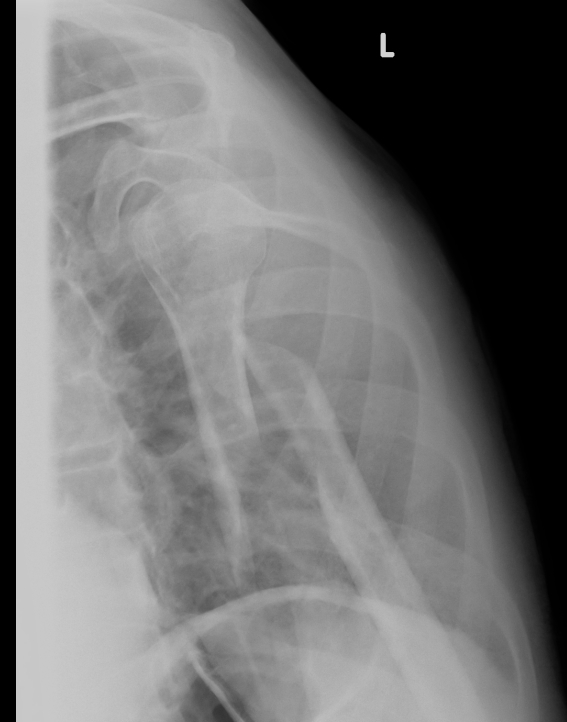

Undisplaced Humeral Fracture APUndisplaced Humeral Fracture Lateral

Displaced Humeral Fracture APDisplaced Humeral Fracture Lateral